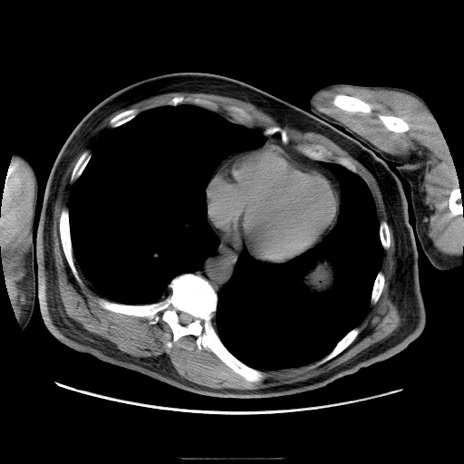

冠状断像

症例22(横断像)

【症例】50歳代男性

【主訴】腹痛

【現病歴】AVMからの被殻出血のため回復期リハ病棟入院中。 本日午後3時頃急に下腹部痛が出現した。

【既往歴】AVM、被殻出血、虫垂炎、高血圧

【身体所見】意識晴明、左半身不全麻痺、会話の理解は良好、36.5°C、腹部:膨隆、全体に板状硬、下腹部正中に圧痛点あり、反跳痛-、筋性防御不明、右下腹部にope scar

【データ】WBC 9400、CRP 0.06